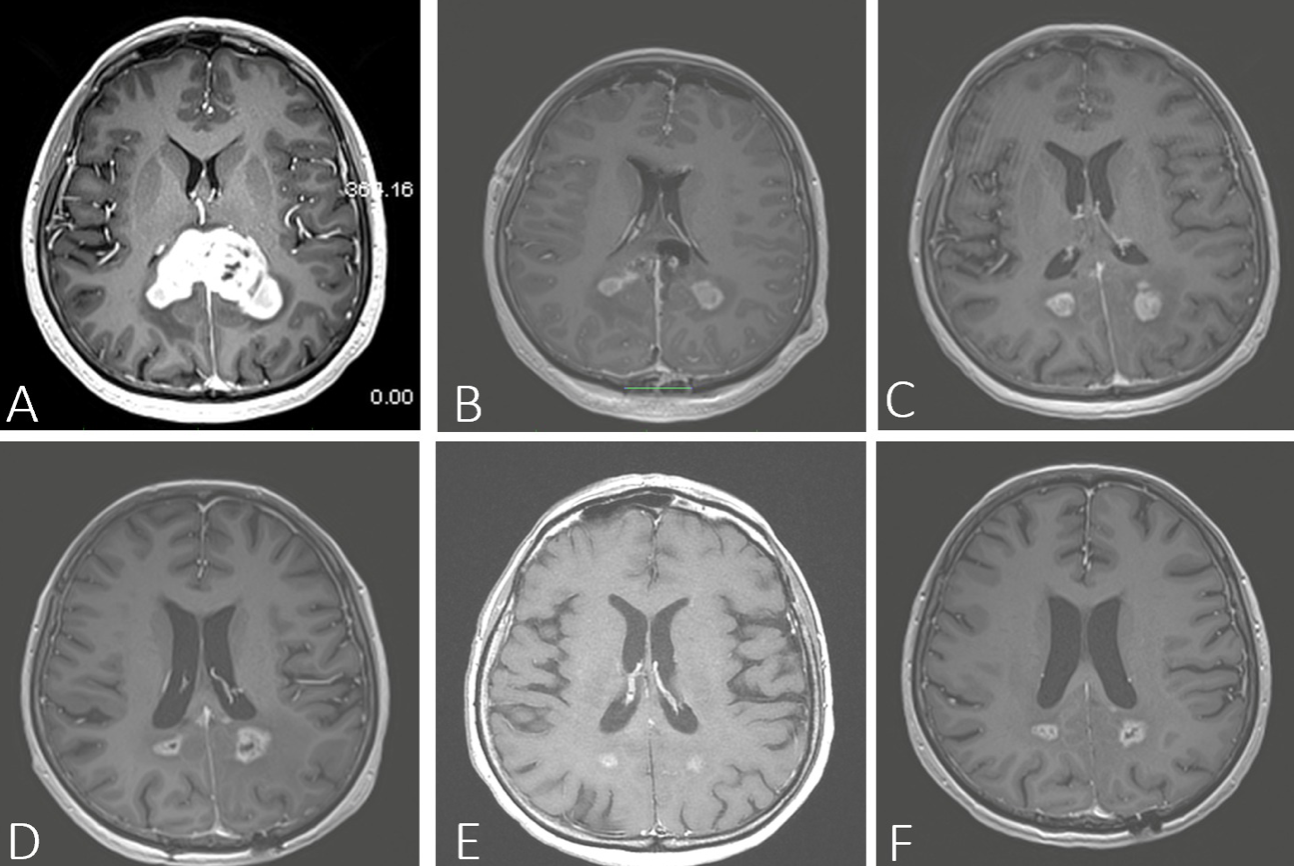

A - RMN preoperator B - Ziua 1 postoperator C - la 3 luni

D - la 6 luni E - la 12 luni F - la 20 de luni

Un caz trimis în mod clasic doar spre biopsie, cu o supraviețuire medie de 6 luni. Prin abord keyhole minim invaziv s-a obținut o rezecție de peste 80% din tumoră. Rezultat: supraviețuire de peste 3 ani.

Intervenția a fost realizată sub monitorizare electrofiziologică continuă în timp real, pentru protecția maximă a funcțiilor neurologice.